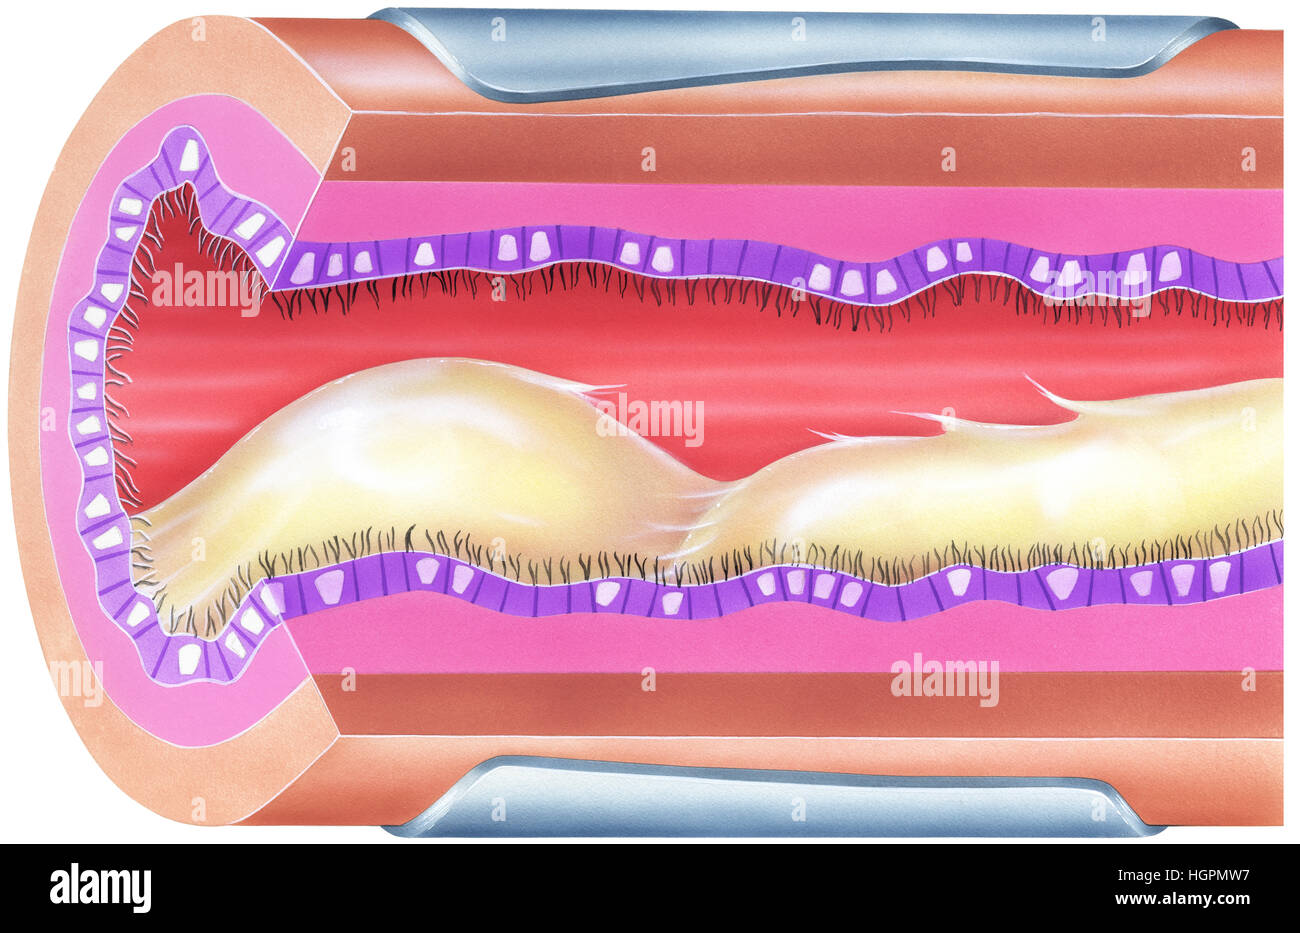

Lungs - Bronchial Mucus. Shown is bronchial airway obstruction and narrowing due to viscid mucus. Stock Photohttps://www.alamy.com/image-license-details/?v=1https://www.alamy.com/stock-photo-lungs-bronchial-mucus-shown-is-bronchial-airway-obstruction-and-narrowing-130806404.html

Lungs - Bronchial Mucus. Shown is bronchial airway obstruction and narrowing due to viscid mucus. Stock Photohttps://www.alamy.com/image-license-details/?v=1https://www.alamy.com/stock-photo-lungs-bronchial-mucus-shown-is-bronchial-airway-obstruction-and-narrowing-130806404.htmlRFHGPMW8–Lungs - Bronchial Mucus. Shown is bronchial airway obstruction and narrowing due to viscid mucus.

Shown is bronchial airway obstruction and narrowing due to viscid mucus. Excessive mucus in bronchial airways can cause significant obstruction and an Stock Photohttps://www.alamy.com/image-license-details/?v=1https://www.alamy.com/stock-photo-shown-is-bronchial-airway-obstruction-and-narrowing-due-to-viscid-130806403.html

Shown is bronchial airway obstruction and narrowing due to viscid mucus. Excessive mucus in bronchial airways can cause significant obstruction and an Stock Photohttps://www.alamy.com/image-license-details/?v=1https://www.alamy.com/stock-photo-shown-is-bronchial-airway-obstruction-and-narrowing-due-to-viscid-130806403.htmlRFHGPMW7–Shown is bronchial airway obstruction and narrowing due to viscid mucus. Excessive mucus in bronchial airways can cause significant obstruction and an